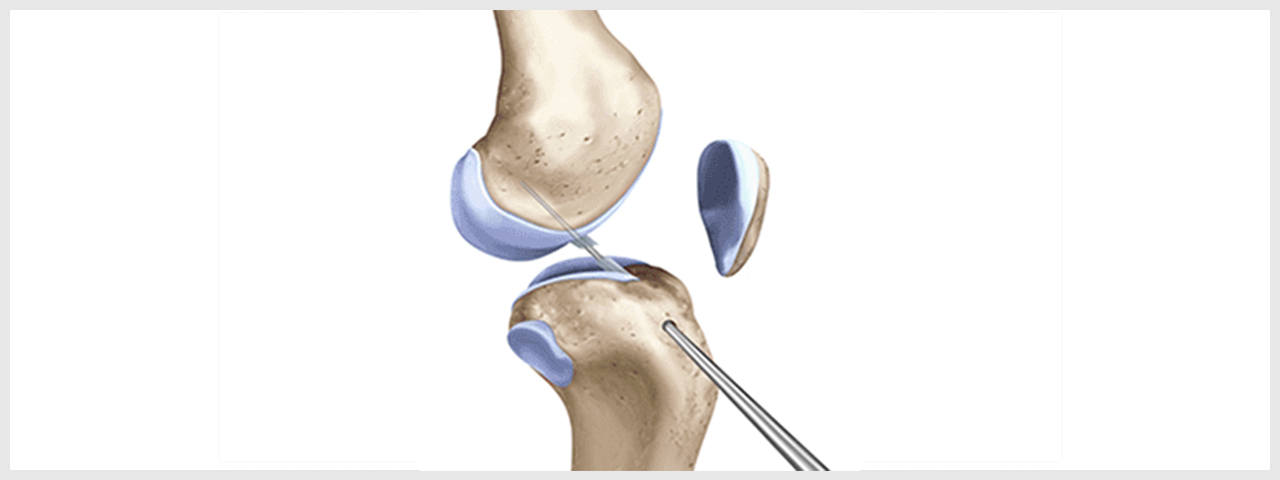

- 최소 절개로 대퇴골과 경골의 병변 부위에 구멍을 내줍니다.

- 터널 구멍을 이용해 이식건을 통과시켜 넣습니다.

- 삽입된 인대를 당긴 후 양측에서 고정하여 새로운 인대 조직이 원래의 인대 강도를 유지하도록 잡아줍니다.